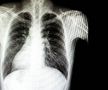

Foto 1/18 : Gazeta Sporturilor prezintă povestea lui Iancu Papazicu, fotbalistul cu inima în partea dreaptă / Fotomontaj Andrei Crăițoiu